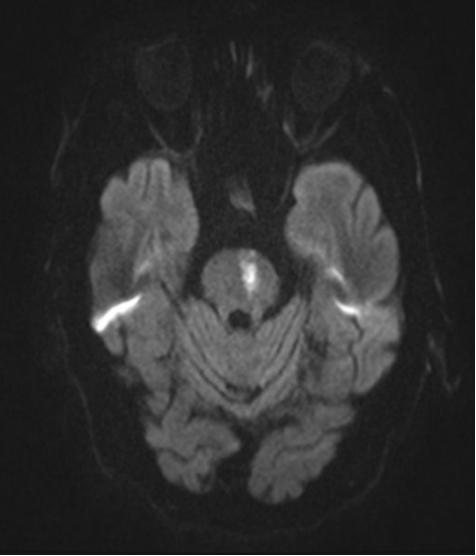

位于脑桥脑梗死病灶,突发的不宁腿,右腿比左腿严重

影像

MRI阴性(原发性RLS)

铁敏感的MRI序列显示:大脑几个区域的铁含量降低(黑质,丘脑,壳核和苍白球)